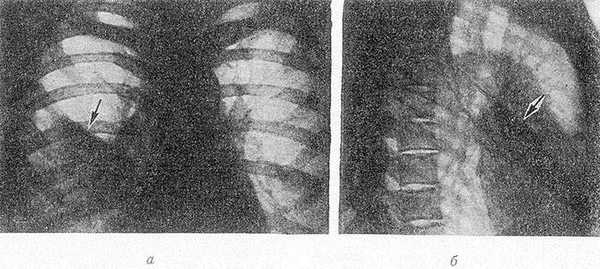

Рис. 1. Рентгенограммы грудной клетки в прямой (а) и правой боковой (б) проекциях при синдроме средней доли: тень пораженной средней доли указана стрелкой.

Рентгенологическое исследование — основной способ распознавания и дифференциальной диагностики изолированных поражений средней доли легкого. При С. д. с. на рентгенограмме грудной клетки в прямой проекции справа от IV ребра и спереди до диафрагмы обычно располагается неправильной формы затемнение с хорошо обозначенной верхней границей (рис. 1, а). На боковой рентгенограмме тень пораженной доли обычно имеет треугольную форму. Границы ее образованы междолевыми щелями; вершина тени направлена к корню легкого, а ее основание — к передней грудной стенке (рис. 1, б). При наличии бронхоэктазов (см.) или полостей распада в легочной ткани (см. Легкие) структура затемнения неоднородна, при цирротических изменениях форма его приближается к клиновидной или лентовидной. В экссудативно-инфильтративной фазе воспалительного процесса, в т. ч. и туберкулезной этиологии, тень пораженной доли обычно сохраняет гомогенный характер и правильную треугольную форму. Томография (см.) лучше, чем обычное рентгенол. исследование, позволяет установить форму тени, определить особенности ее контуров и структуру патологического очага. Послойное рентгенол. исследование наиболее информативно при наличии увеличенных лимф, узлов, участков деструкции, бронхоэктазов, обтурации среднедолевого бронха.